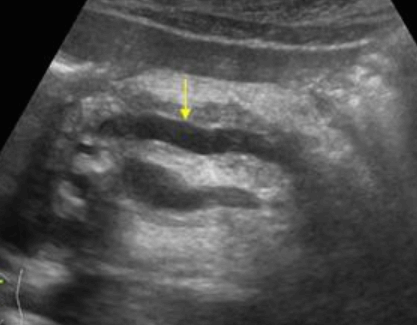

- 간문부와 직경이 큰 문맥관 주변에 호발 한다.

- portal vein을 따라 산재된 낭성병변 (포도송이 모양)

- 원인은 주로 간경변, 알코올성 간질환이 심한 환자에서 발견된다.